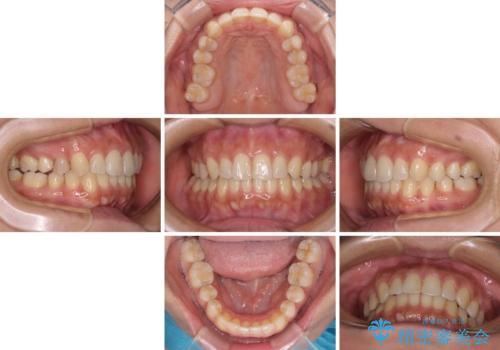

沖縄から飛行機で通院 インビザラインによる矯正治療

- 患者様

- 30代女性

- 矯正装置

- インビザライン

- 治療期間

- 3年8ヶ月

- 定期的に東京に来るので、沖縄から矯正治療で通院したいとのことで来院された患者様です。

歯列不正は軽度であったので、応急処置の少ないインビザラインにて矯正治療を行うこととしました。

通院途中に、仕事の都合で東京に来る機会が激減してしまったため、なかなか治療が進まず、当初終了予定であった時期が2年近くずれ込んでしまいました。

今後もむし歯治療が必要となるため、日程を調整して沖縄から通院されるとのことでした。